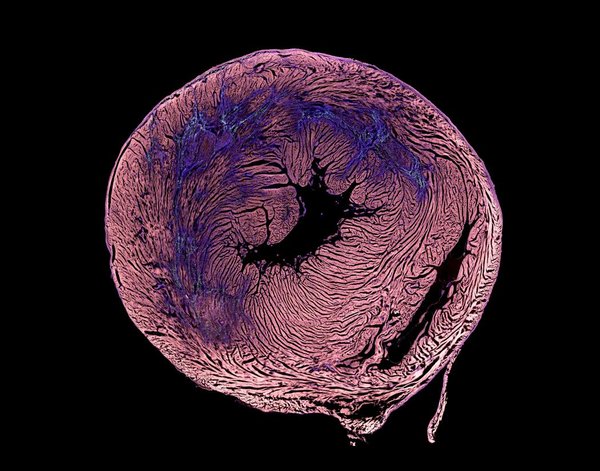

The Evident VS200 is a research-grade slide scanner, designed to capture high-resolution images of slides for quantitative analysis. The system can hold up to 210 26x76 mm slides in 35 sample trays, with robotics that automatically load and unload trays. The system can image up to 60x, with an automated oil dispenser. This system is fantastic for tissue sections, blood smears, and other slide-mounted samples.

• Brightfield with RGB color camera for imaging common tissue stains

• Polarized light for improved contrast and tissue classification (picosirius red)